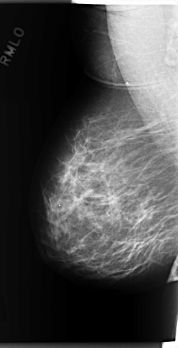

C_0277_1.RIGHT_MLO

RIGHT_MLO LINES 5904 PIXELS_PER_LINE 3024 BITS_PER_PIXEL 12 RESOLUTION 50 NON_OVERLAY